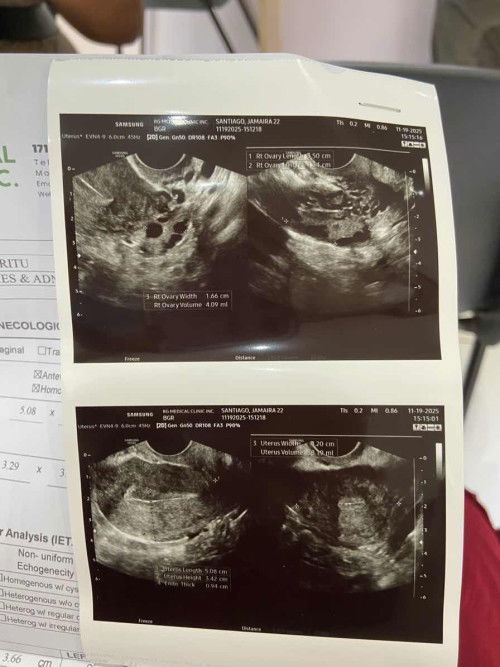

2 months delay pcos poba ito? ask lang po

no pcos. your ovaries are normal. i experienced that but due to hormonal imbalance due to stress.